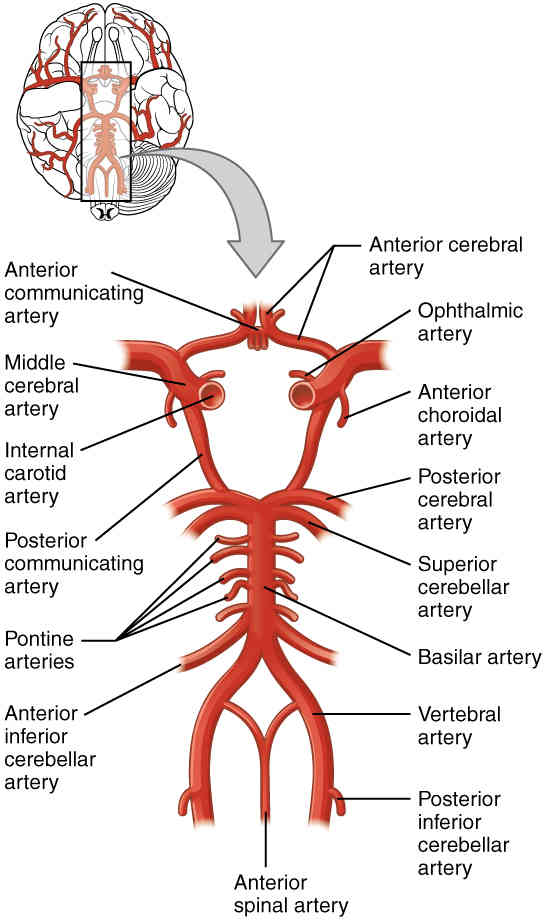

This page is under construction. For now, it is just a resource of the images found in the OpenStax Anatomy and Physiology Handbook. It wil slowly change into a revision tool. Each slide has a number. Use this to refer to the slide. When completed, it will have an unlabelled section, with labelled slides in parallel. On the unlabelled slides, write your answer and use the labelled slide to assess yourself. Keep track by also noting the number on each slide. Improvement at each attempt is important, more so than full marks on a first attempt.